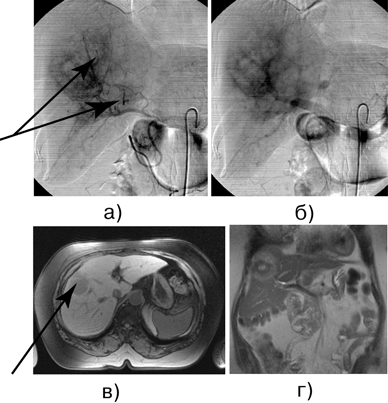

Рисунок 2. Б-ная И., 64 года. Рак прямой кишки, состояние после брюшно-промежностной экстирпации прямой кишки. Метастаз аденокарциномы прямой кишки в правую долю печени:

а — целиакография, поздняя артериальная фаза, метастатический узел в правой доле печени; б — целиакография, венозная фаза, метастатический узел в правой доле печени; в — МРТ: поперечный срез, метастатический узел в проекции V-VIII сегмента; г — МРТ: фронтальный срез, метастатический узел в проекции V-VIII сегмента.

В дальнейшем выполнена правосторонняя гемигепатэктомия